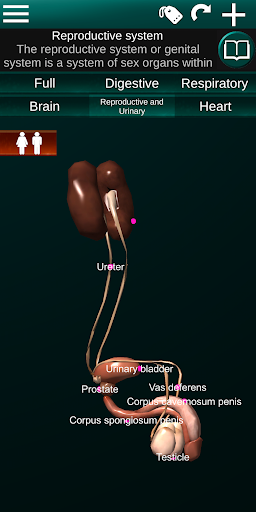

Internal Organs in 3D Anatomy لـ Vodafone Smart N9 Lite

(الأجهزة الداخلية في)

Internal Organs 3D Anatomy 3.4

يمكنك هنا تنزيل ملف حزمة تطبيق أندرويد "Internal Organs 3D Anatomy" الخاصة بجهازVodafone Smart N9 Lite مجانًا، نسخة ملف حزمة تطبيق أندرويد - 3.4 للتحميل على Vodafone Smart N9 Lite اضغط ببساطة على هذا الزر. إنه سهل وآمن. نحن نقدم فقط ملفات حزمة تطبيق أندرويد الأصلية. إذا انتهكت أية مواد موجودة في الموقع حقوقك قم بإبلاغنا من خلال